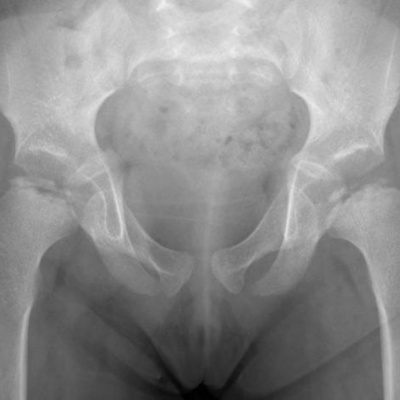

In this podcast, I reflect on my encounter with the childhood hip disorder, Perthes, and recount some of the barbaric treatments myslef and my fellow sufferers had to put up with back in the 1970s. Ultimately, I learn that writing a funny silly peom about the whole sorry episode, in a northern accident, may not bring closure, but does help to place the illness in the context of a wider life of shite.